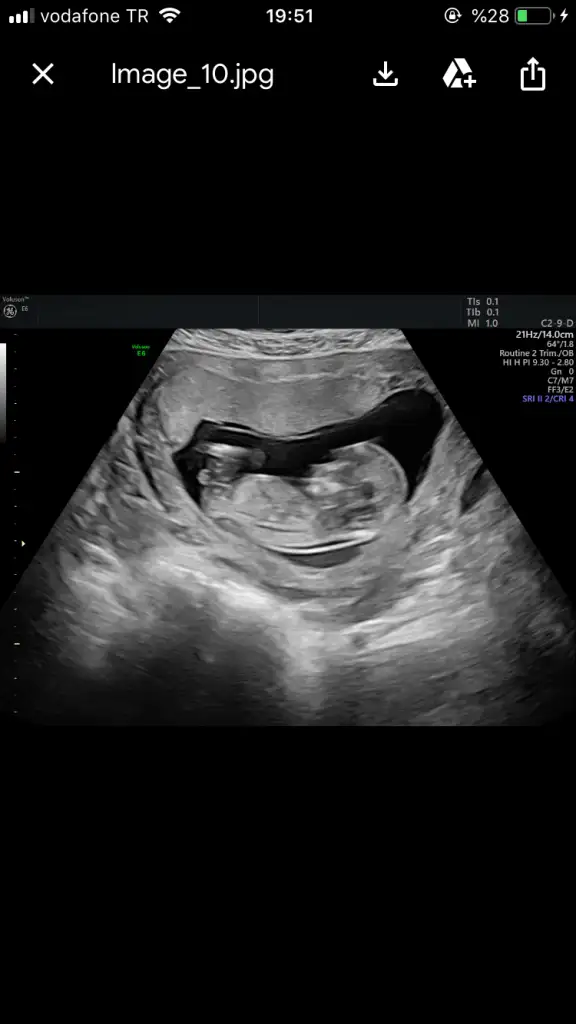

En son 12+4 de baktı canım heryeride kıpır kıpır görünüyordu ama 16dan önce sölemiyormuşmuşEn son nezman dr ultrasyonla bakdi cnm sana?

Benimkide aynı öyle ellerini karnına koymuş bi ellerini kaldırıp indiriyodu kurban olurumBenim bebe kalbi atıyordu hiç hareket etmiyordu ayakları çapraz yapmis yan yatıyordu

Ayyy yaa bak icim kıpırdadı sütüm olsa akardiBenimkide aynı öyle ellerini karnına koymuş bi ellerini kaldırıp indiriyodu kurban olurumoğlumda maşallah bu zamanlarda eller kollar dans ediyodu. Naif bi kız olcak belli

Benim kız hep öleydiBenim bebe kalbi atıyordu hiç hareket etmiyordu ayakları çapraz yapmis yan yatıyordu

Aynı benimki kıçı başı ayrı oynuyodu ama cinsiyet olunca doktor pozisyonu kötü dediBenim kız hep öleydiBuda tam tersi ters dönmüş böcük gibi eller kollar havada kıpır kıpır kıpırdıyordu ayaklarıyla keseye vurup vurup hoplatıyordu kendini tontirikimmmm

Ay seninki gene kötü demiş göremiyom demek istemiş benim doktor çok yardımsever bi çocuk ne güzel poz veriyor hiç yormadı ölçümlerini alabildim dedi uleeee hiç mi görmedin orayıAynı benimki kıçı başı ayrı oynuyodu ama cinsiyet olunca doktor pozisyonu kötü dedi